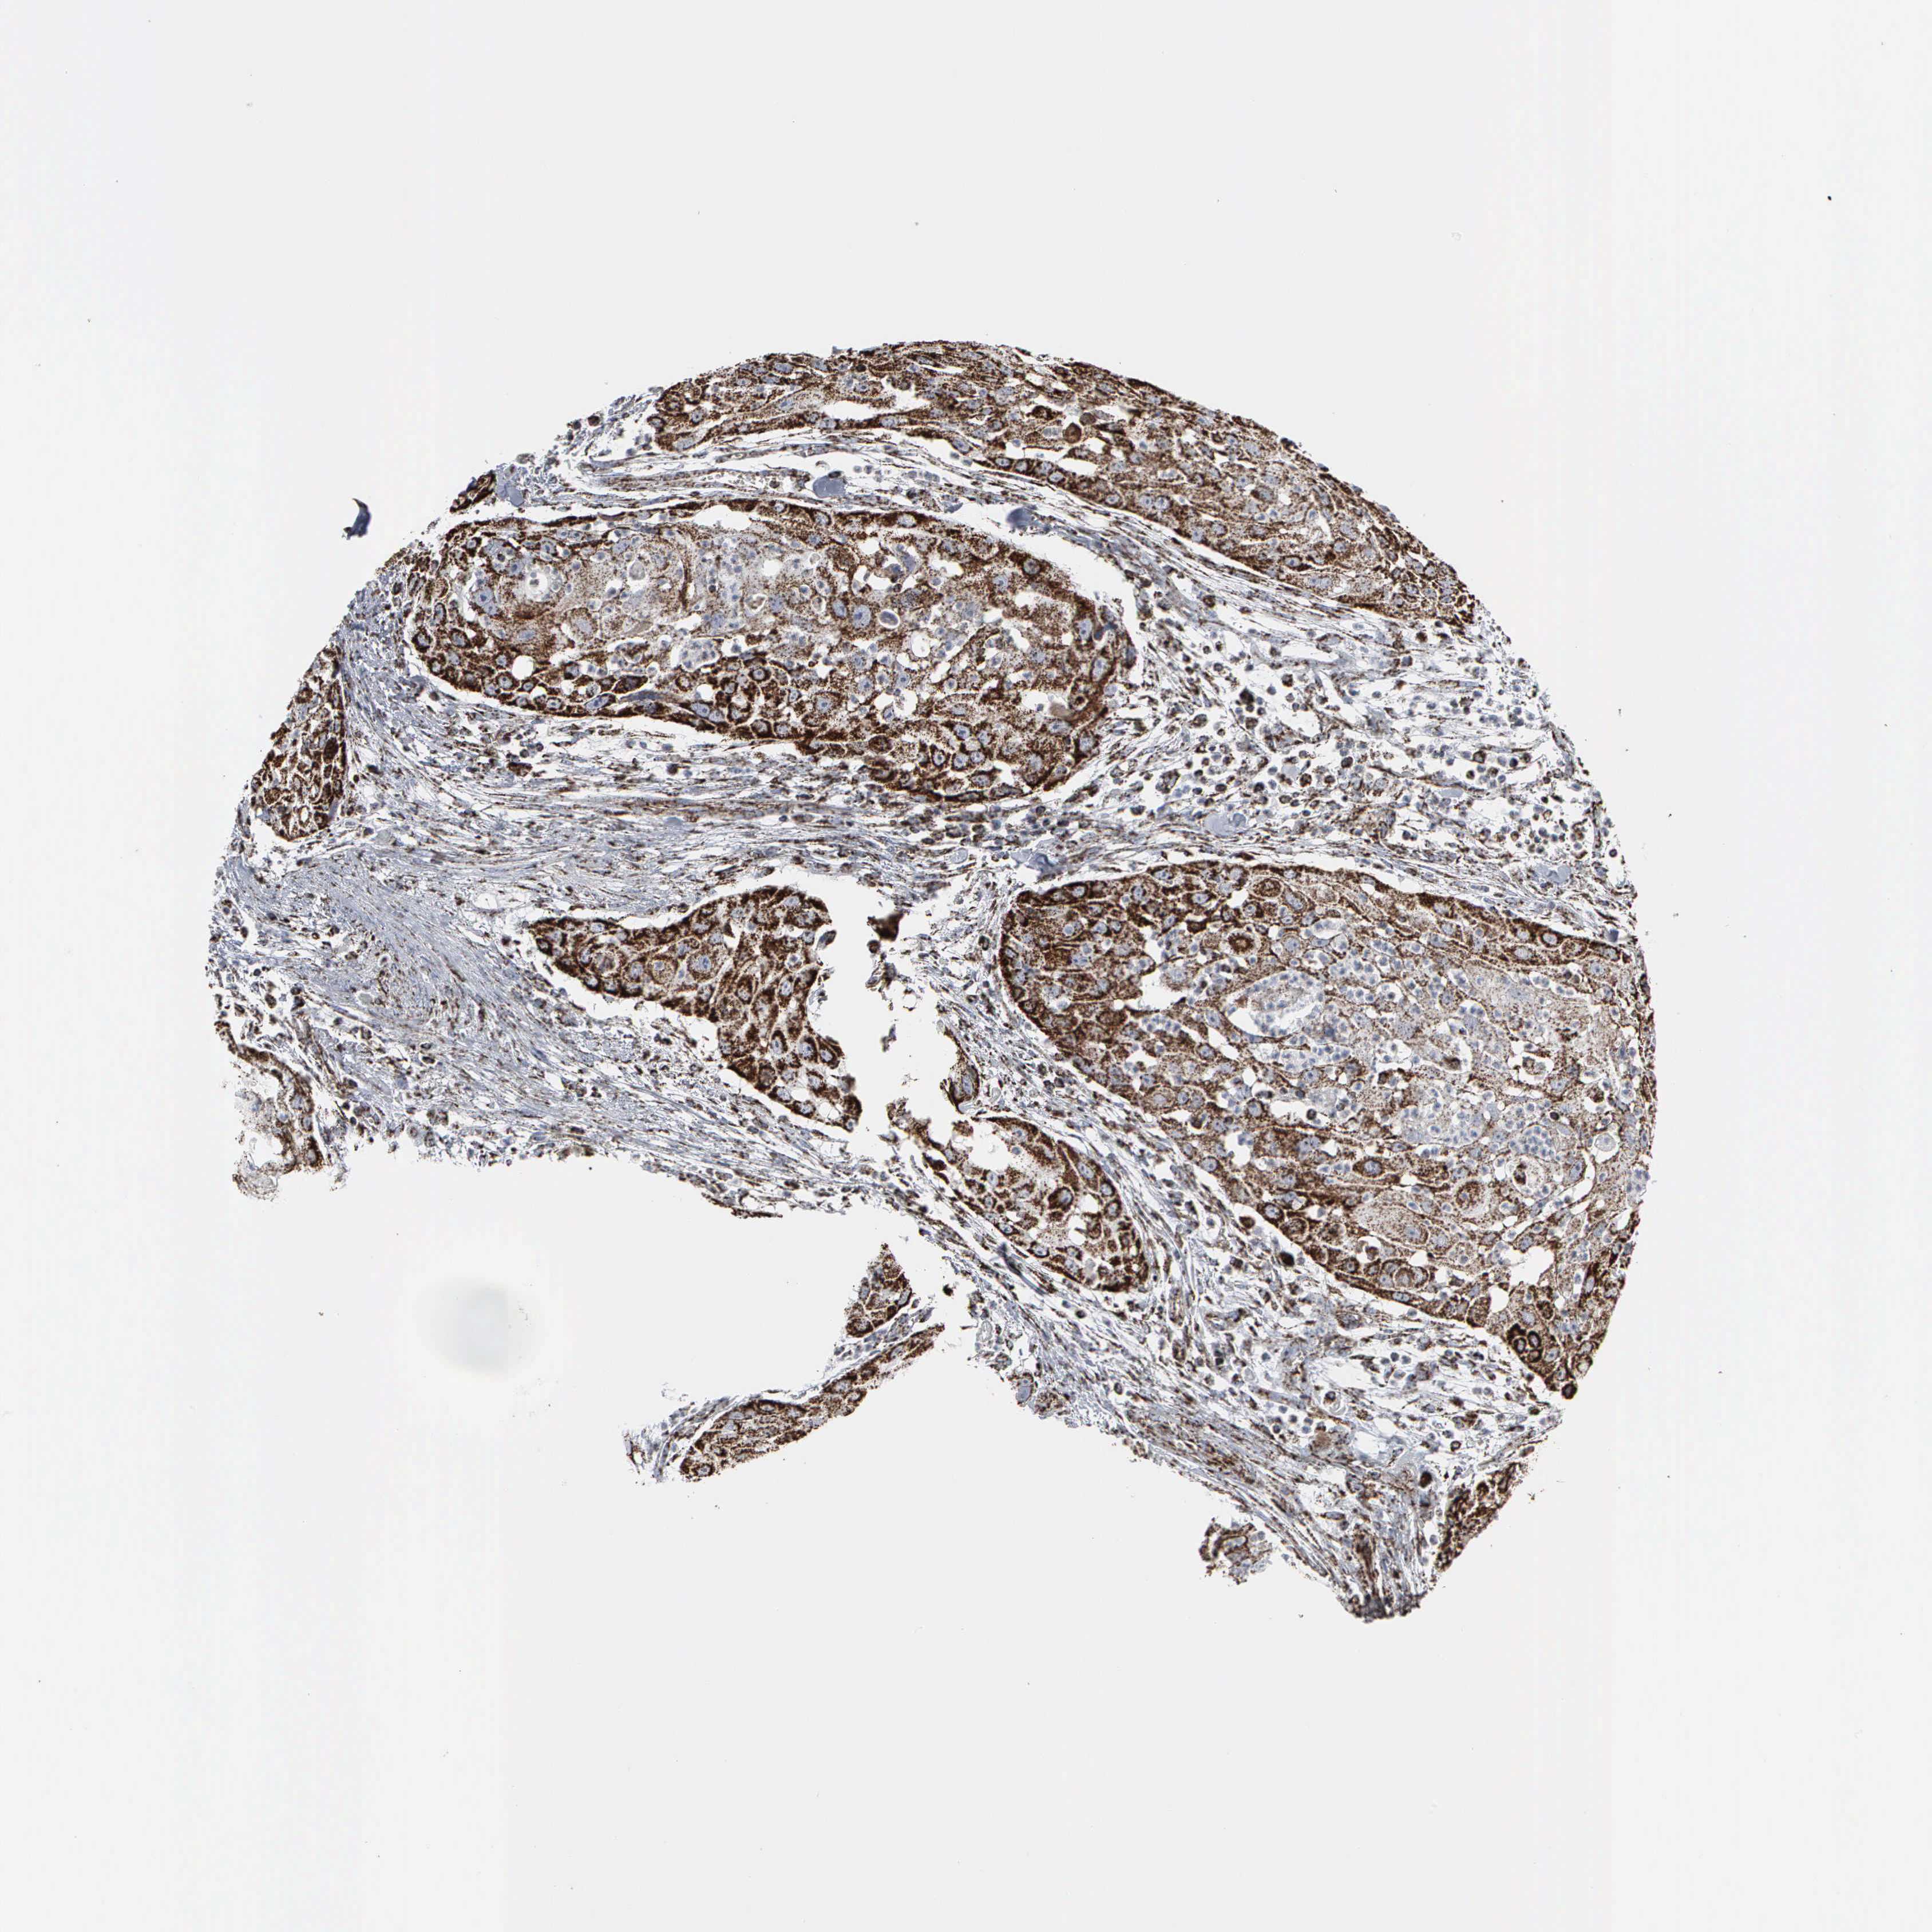

HEAD AND NECK CANCER - Protein expressioni

A mouse-over function shows sample information and annotation data. Click on an image to view it in a full screen mode. Samples can be filtered based on level of antibody staining by selecting one or several of the following categories: high, medium, low and not detected. The assay and annotation is described here.

Antibody stainingi

Antibody staining in the annotated cell types in the current human tissue is reported as not detected, low, medium, or high, based on conventional immunohistochemistry profiling in selected tissues. This score is based on the combination of the staining intensity and fraction of stained cells.

Each image is clickable and will lead to virtual microscopy that enables deeper exploration of all samples and also displays staining intensity scores, fraction scores and subcellular localization as well as patient and tissue information for each sample.

Antibody HPA000898

Antibody CAB005219

Staining

High

Medium

Low

Not detected

Intensity

Strong

Moderate

Weak

Negative

Quantity

>75%

75%-25%

<25%

None

Location

Nuclear

Cytoplasmic/membranous

Cytoplasmic/membranous,nuclear

Squamous cell carcinoma, NOS

Squamous cell carcinoma, metastatic, NOS

Adenocarcinoma, NOS

Adenoma, NOS